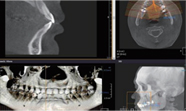

• 3D 구강 스캔을 통한 진단 및 가이드 제작

3D 디지털 검진, 디지털 스캐닝을 통해구강 내부를 정밀하게 진단하고

환자분의 인상을 채득합니다.